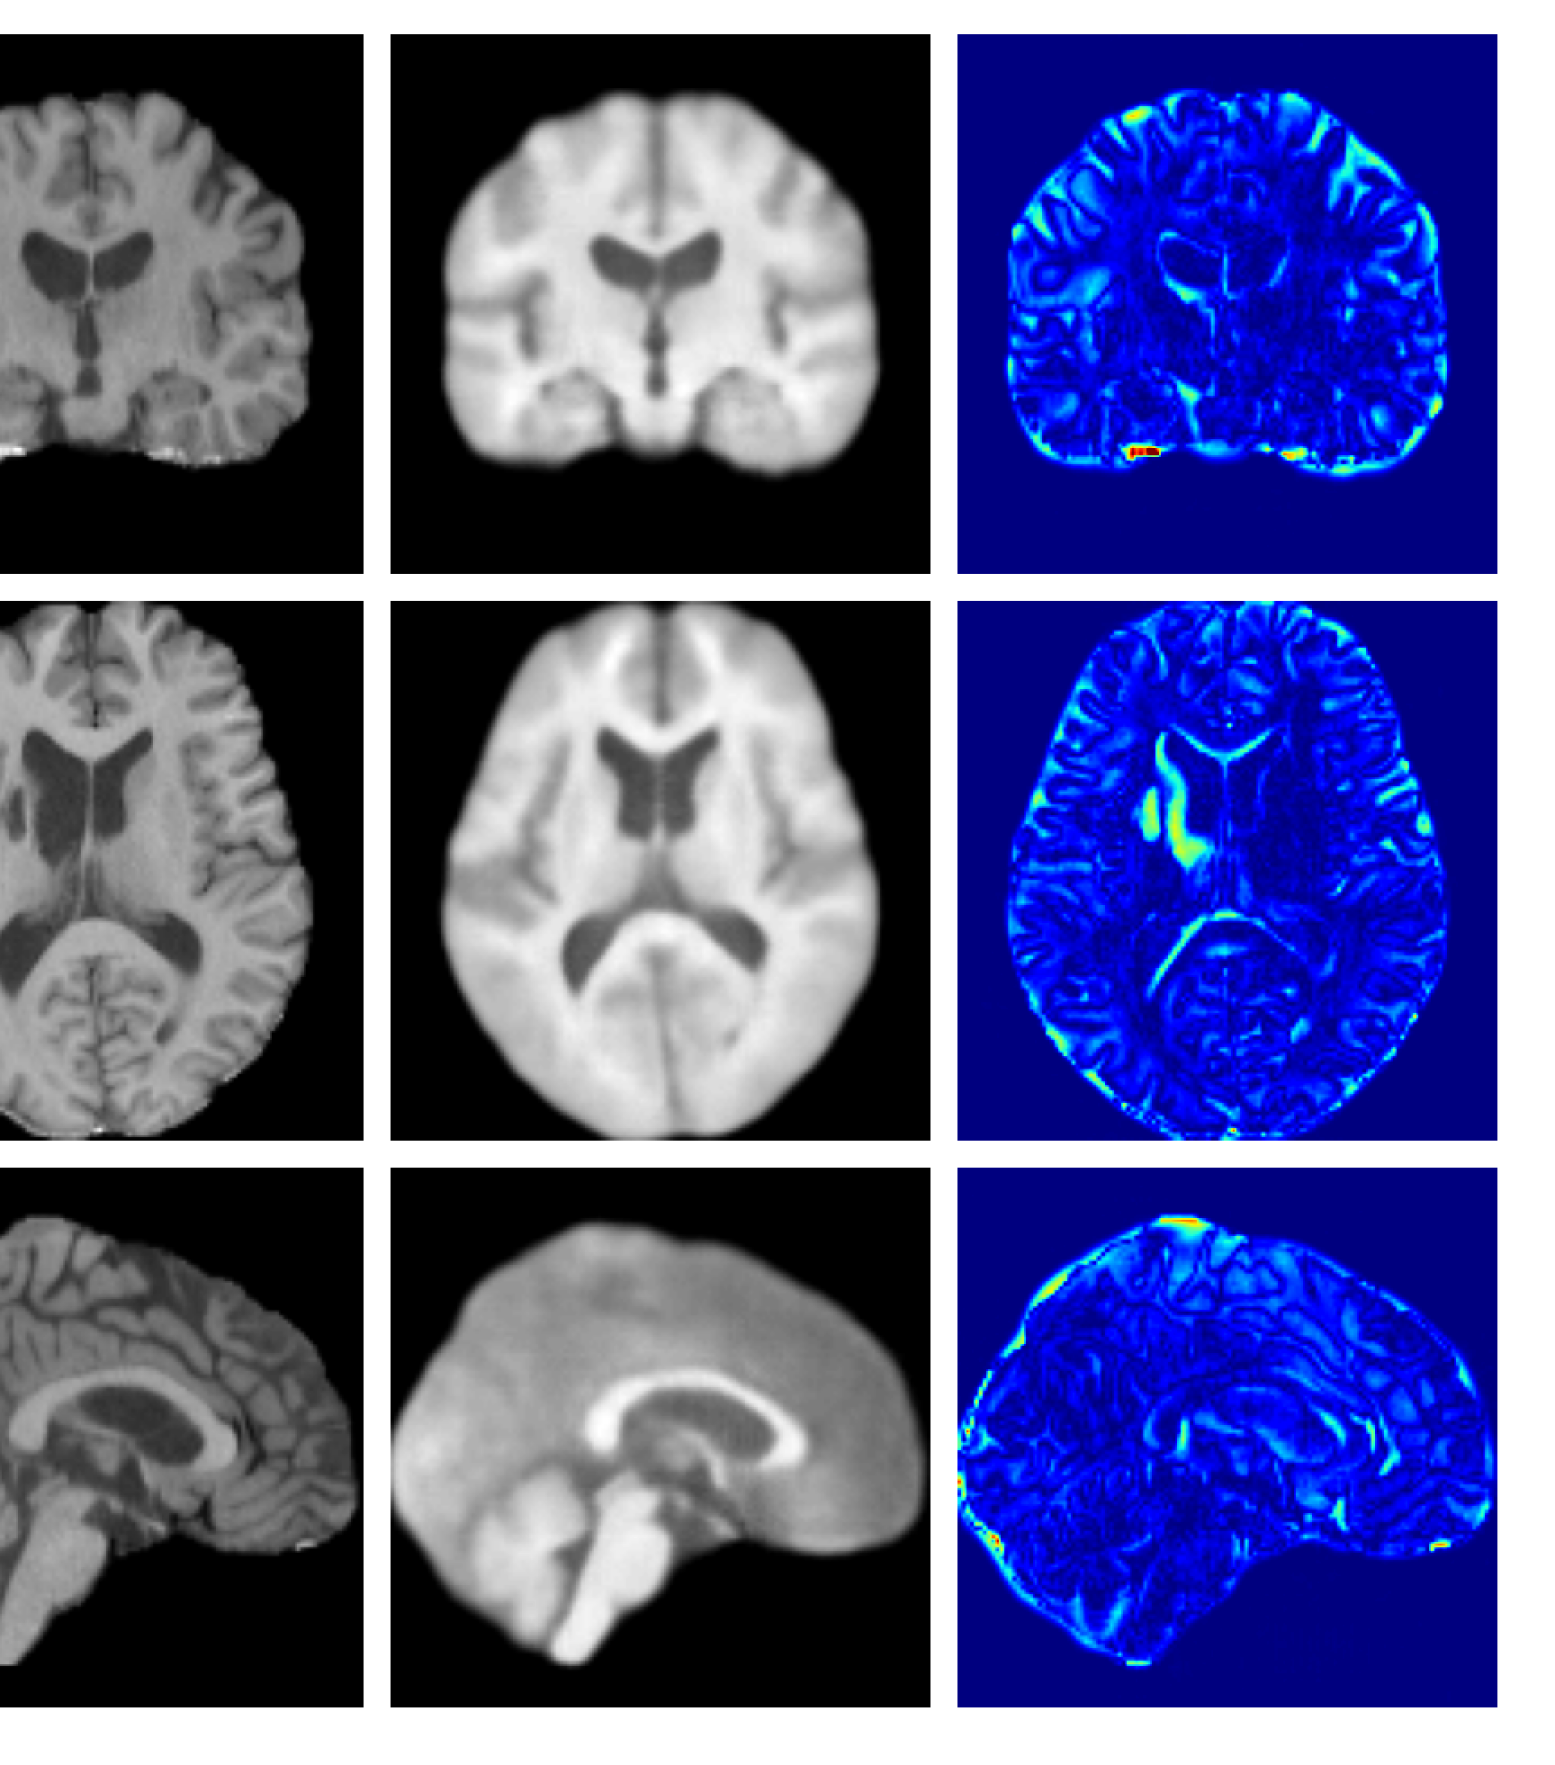

Figure 3: Example reconstructions and anomaly maps for a sample from the disease cohort of the UKBB dataset. Lesion and WMH are indicated in the original image by the red and yellow boxes respectively.

Figures 3 and 4, show example reconstructions and abnormality maps for a sample from the UKBB and UoTH datasets, respectively. Enlarged figures and additional example qualitative results for the ADNI dataset are available in the Supplementary. In Figure 3 we see that whilst all models are able to detect the lesion visible in the sagittal slice, the VAE, cVAE, LDM and LDM (TavgT_{avg}) produce very smooth outputs or lose defining characteristics and thus exhibit more false positives in healthy tissue. THOR and CADD provide the best results, with CADD better detecting white matter hypointensities (WMH). However, neither method fully inpaints all WMH, potentially due to presence of WMH in the healthy training set.

Figure 7 provides example reconstructions and anomaly maps for a healthy subject from the UK Biobank holdout test cohort.

Figure 7: Example healthy reconstructions and anomaly maps for a sample from the UK Biobank healthy test cohort. For a healthy subject, we should observe no regions highlighted in the anomaly map.